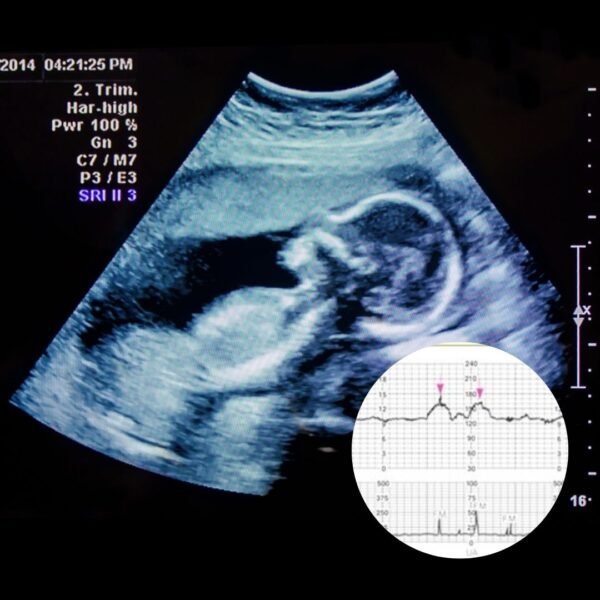

Biophysical scoring, specifically the Biophysical Profile (BPP), assesses fetal well-being through ultrasound measurements of breathing, movement, tone, and amniotic fluid, with results added to a Non-Stress Test (NST) score to give a total score from 0-10. A “reactive” NST (fetal heart rate accelerates with movement) is given 2 points, while a “non-reactive” one gets 0 points.

A final BPP score of 8–10 is generally normal, while lower scores may indicate fetal distress and require more evaluation or intervention.

Ultrasound Report + Thermal Prints+NST Strip

- Growth Measurements

- Fetal presentation

- Placental localization

- Amniotic Fluid Volume

- Observational Movement

- Audible Heartbeat trace (fetal heart rate – FHR)

- Dating of Pregnancy (age of gestation-AOG)

- Estimates current fetal weight (estimated fetal body weight – EFBW)

- Estimates due date (estimated date of delivery – EDD)

- Complimentary Gender Evaluation by request

(subject to baby’s position and structural limitations)